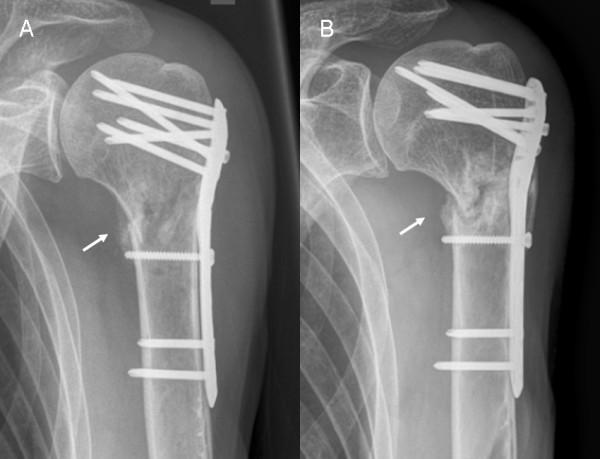

Follow-up was possible in 60 patients (C+ 6.7 ± 5.6 M/C- 5.0 ± 2.8 M). Humeral head necrosis occurred in 6 (C+, 15.4%) and 3 (C-, 14.3%) cases. Cut-out of the proximal screws was observed in 3 (C+, 7.7%) and 1 (C-, 4.8%) cases. In each group, 1 patient showed delayed union. Implant failure or lesions of the axillary nerve were not observed. In 44 patients, true AP and Neer views were available to measure the head-plate distance. There was a significant loss of reduction in group C- (2.56 ± 2.65 mm) compared to C+ (0.77 ± 1.44 mm; p = 0.01).

结果

60 例患者(C+组 6.7 ± 5.6 M/C-组 5.0 ± 2.8 M)获得随访。C+组有 6 例(15.4%)和 C-组有 3 例(14.3%)发生肱骨头坏死。C+组有 3 例(7.7%)和 C-组有 1 例(4.8%)发生近端螺钉切出。每组各有 1 例患者发生延迟愈合。未观察到内固定物失败或腋神经损伤。在 44 例患者中,可获得正位和 Neer 位 X 线片来测量头-板距离。C-组的复位丢失明显多于 C+组(2.56 ± 2.65 mm 比 0.77 ± 1.44 mm;p = 0.01)。